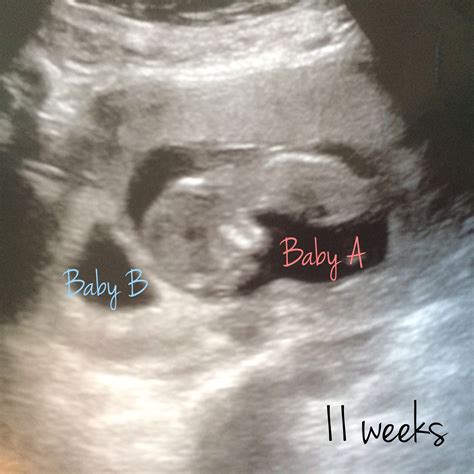

• Embryo: At 4 weeks, the embryo itself is very small, often measuring less than 1 mm. It may not be visible on the ultrasound, but the presence of the gestational and yolk sacs is a positive sign.

• Positive Results: The presence of a gestational sac and yolk sac indicates a viable pregnancy. The healthcare provider will discuss the next steps, including scheduling future ultrasounds and prenatal appointments.

It's important to remember that every pregnancy is unique, and the results of an early ultrasound can vary. Your healthcare provider will guide you through the next steps based on the findings.